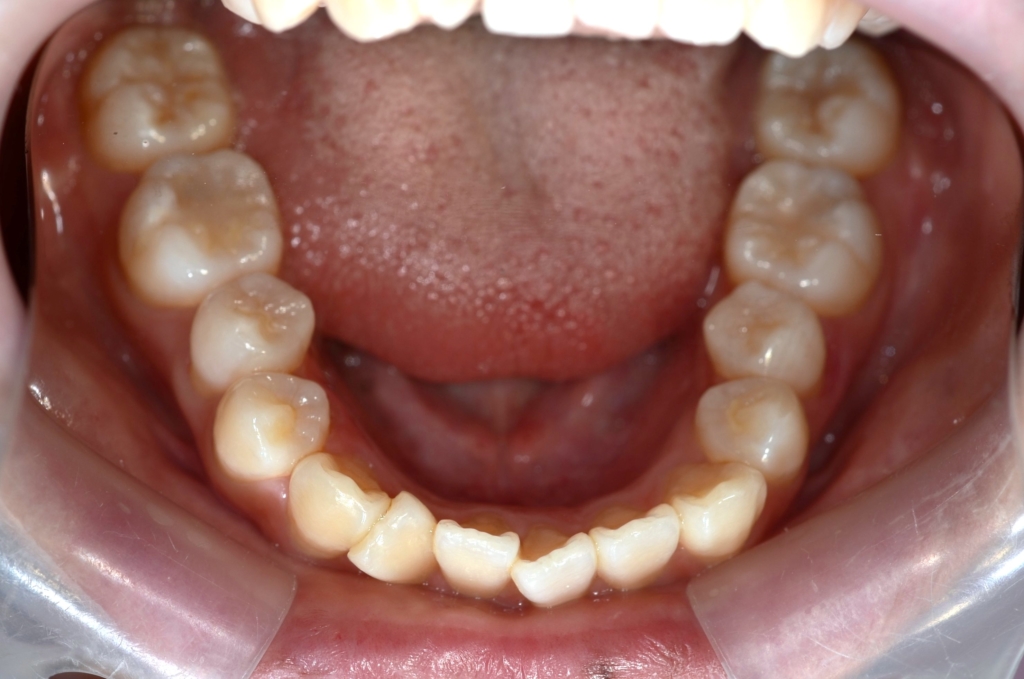

ついでに、歯並びの比較です

上段が矯正治療前、下段が矯正治療後